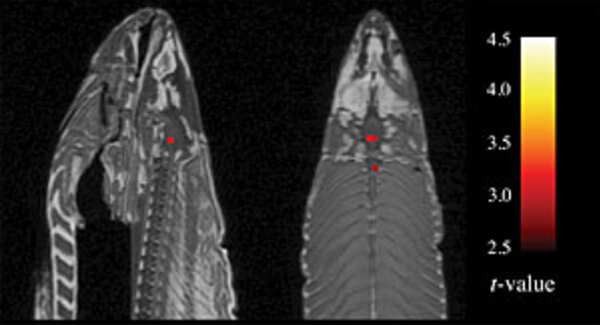

L'incroyable histoire du saumon mort qui pensait encore

En juin 2009, à l'occasion du congrès HUMAN BRAIN MAPPING, un poster retint particulièrement l'attention. Pourtant les auteurs n'y faisaient rien...

490  1